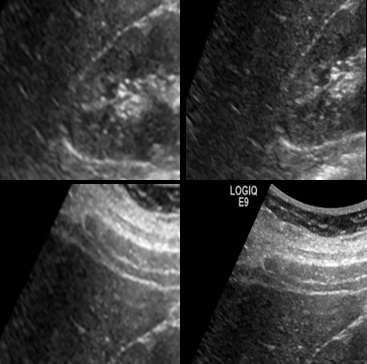

It is indeed very interesting to see that features learnt on camera images were able to outperform careful feature engineering on sharply different detection problems, in modalities whose acquisition physics are distinctly different. Fig. 4 compares some of the response images generated from layers 1 and 2 of the learned network with traditional image processing outputs like Phase Congruency [14] and Frangi vesselness filter [9] for an example patch.

Here, we would like to highlight two main points: (1) Visually, we find the output has intriguing similarities with the outputs of hand crafted feature extractors optimized for Ultrasound. The response maps of Fig. 4LABEL:sub@subfig:CNFA_L11 and LABEL:sub@subfig:CNFA_L2 are similar to 4LABEL:sub@subfig:PC and LABEL:sub@subfig:frangi. This is very encouraging because of the fact that CNNs learns features that are equivalent to some of these widely used non-linear feature extractors. (2) The second important observation here is the reduction in speckle noise on CaffeNet_FAL1_1, compared to CaffeNet_PAL1_1. By carefully tuning CaffetNet features on ultrasound data, the model was able to learn the underlying noise characteristics, while preserving edges, and this resulted in a much improved response map as shown in Fig. 4LABEL:sub@subfig:CNFA_L11 and LABEL:sub@subfig:CNFA_L2.